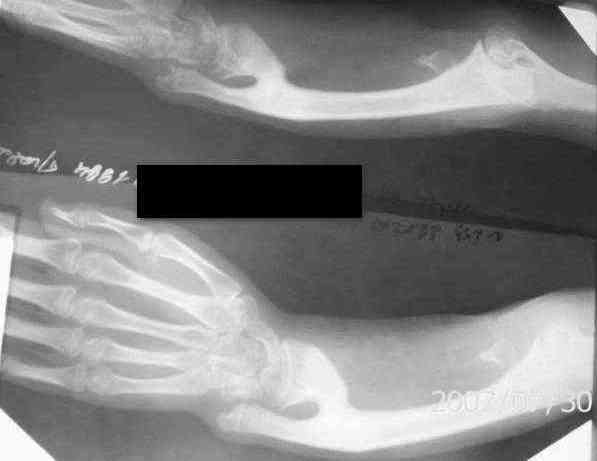

К нам обратилась девочка 12 ти лет с жалобами на деформацию левого

предплечья. Девочка перенесла сепсис ,остеомиелит лучевой кости в возрасте 4х лет.

Клинически выражена лучевая косорукостью, просупинационные движения

отсутствуют, сгибание в локтевом суставе в полном объеме.